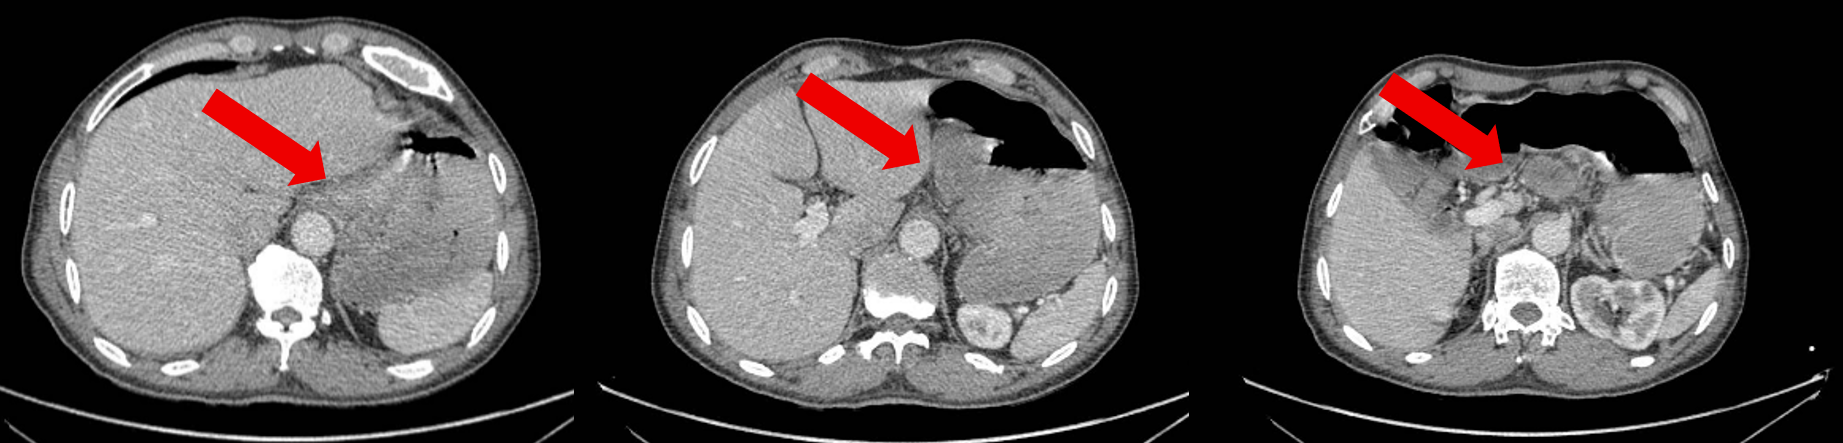

基线情况:2024-8-9全腹部CT提示胃底、胃体小弯侧胃壁不均增厚,病灶较厚处约2.8cm。贲门左、胃小弯及肝胃间隙数个增大淋巴结,大者大小约4.6×3.1cm。

治疗2周期后患者于2024-10-20复查腹部CT:胃底、胃体小弯侧胃壁不均增厚,与邻近贲门分界不清,较前减轻,病灶较厚处约1.3cm。贲门左、胃小弯及肝胃间隙数个增大淋巴结,多系转移,多数较前缩小,大者大小约3.0×1.7cm。